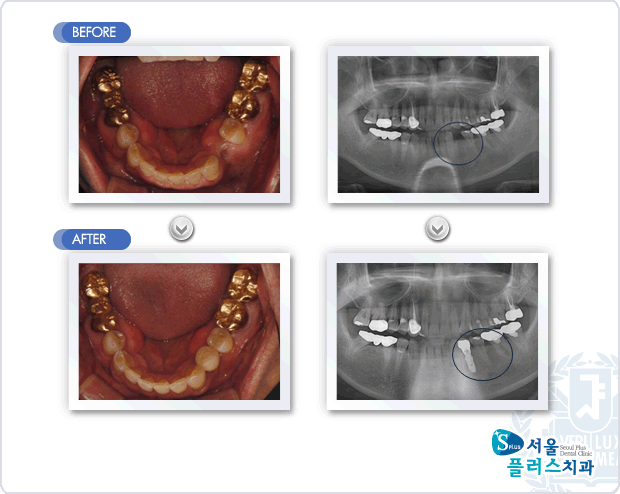

[임플란트] 하악 좌측 제1소구치 발치후 내원